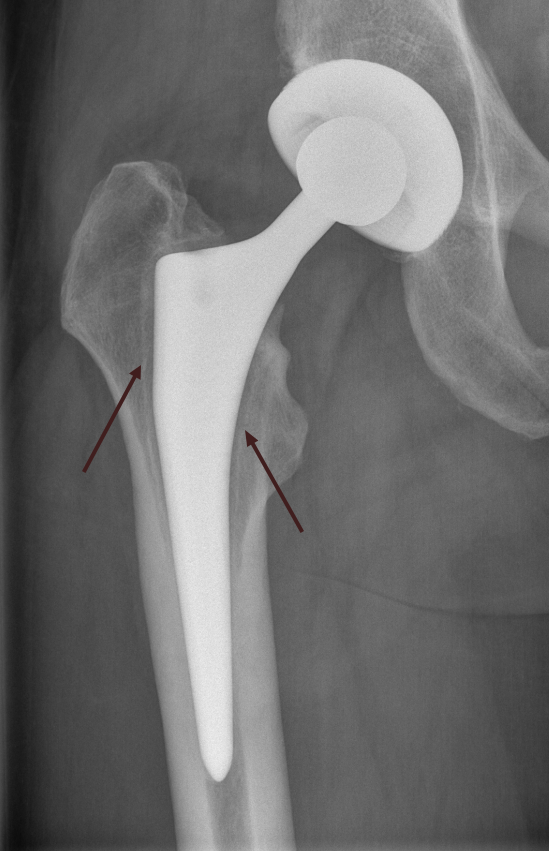

Für die Ursachenfindung bei schmerzhafter Hüftprothese ist eine detaillierte Patientenbefragung (Anamnese) wichtig. Wichtig ist zu erfahren, seit wann die Beschwerden genau bestehen und ob es einen Auslöser dafür gab. Neben der Lokalisation der Schmerzen ist es ebenfalls wichtig zu wissen, wann der Schmerz genau auftritt (immer, nur bei Belastungen, nur bei gewissen Bewegungen). Informationen zu Nebenerkrankungen, durchgemachten Infektionen oder erfolgten Zahnbehandlungen sind ebenfalls notwendig. Nach der Patientenbefragung findet eine Inspektion und detaillierte klinische Untersuchung statt. Dabei werden die möglichen Ursachen weiter eingegrenzt. Zusätzlich wird ein konventionelles Röntgenbild der Hüfte aufgenommen. Anhand diesem kann in gewissem Masse bereits die Prothesenlage und eine allfällige Lockerung beurteilt werden.

Im Vergleich zum Vorbild (links) zeigt sich im konventionellen Röntgenbild (rechts) ein Lockerungssaum (aus Bindegewebe) um den Prothesenschaft.

Bilder: Universitätsklinik Balgrist